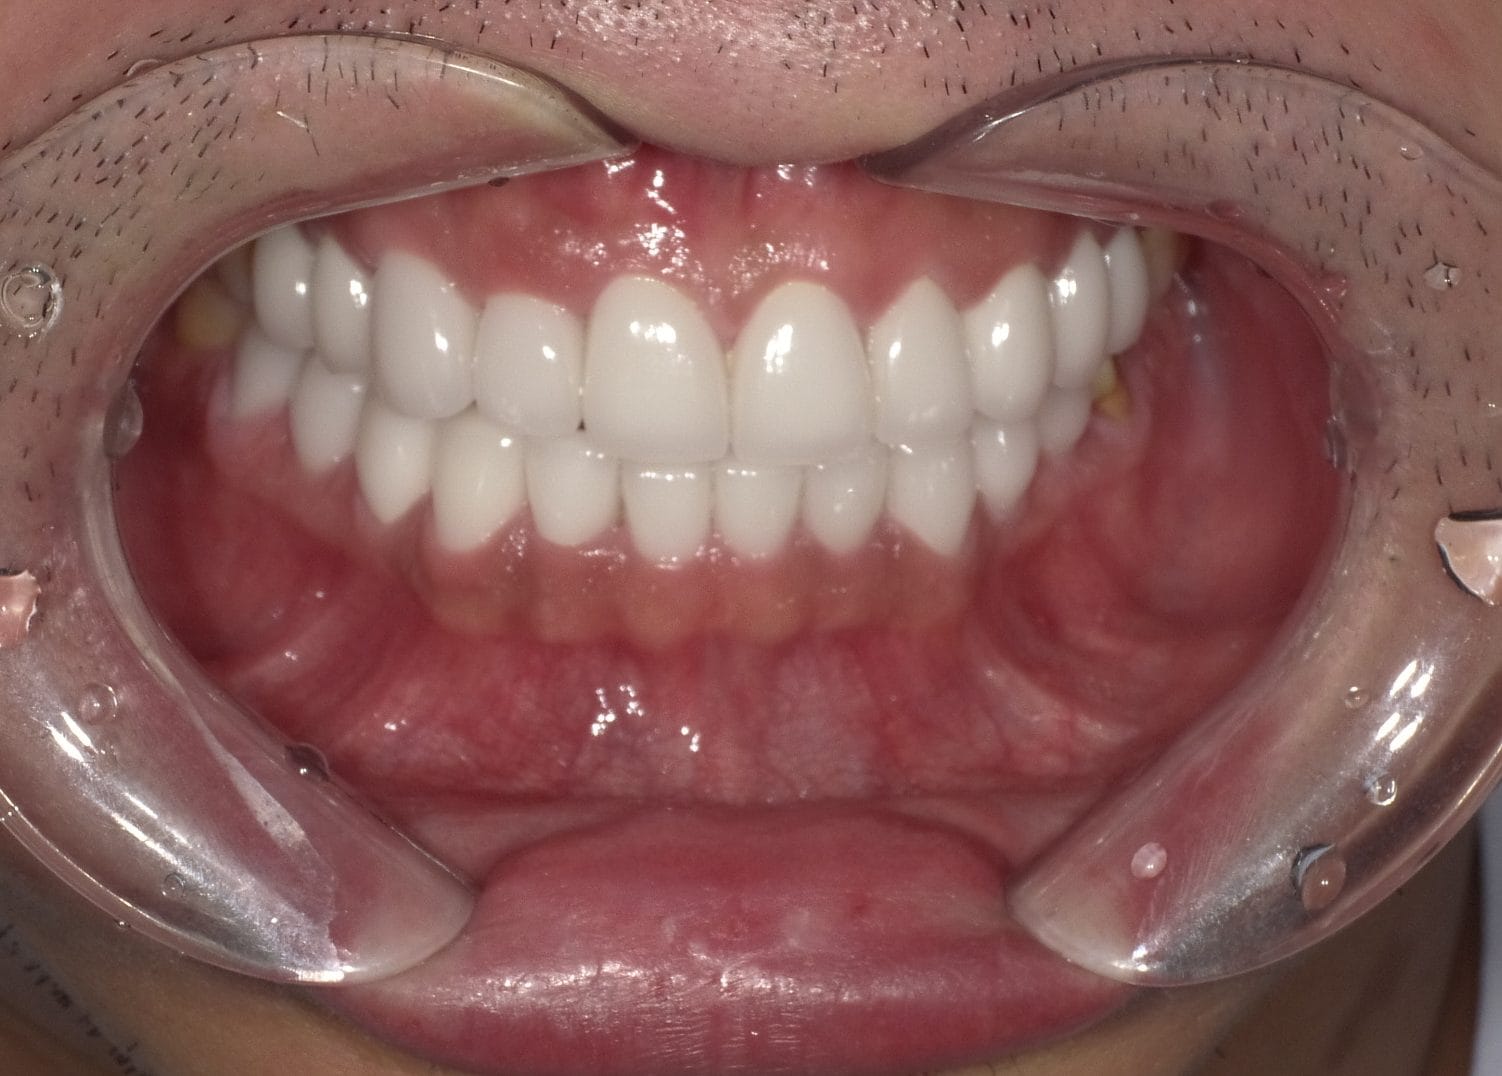

Case029

セラミック矯正の患者様です。

・上下の歯の入れ違い

・正中の歪みと隙間

を主訴にご来院くださいました。

この患者様は若年性歯周炎にかかってしまったため、一生懸命に歯を磨き、口の中は綺麗なのにも関わらず歯茎が下がってしまい、隙間が出来てしまっています。

これは矯正治療で歯の並び方を変えても絶対に無くなりません。

そのため、患者様の主訴を叶えるためにセラミック矯正で治療計画を練りました。

前のクリニックでは「上下一本ずつ抜糸してブリッジで矯正する」という計画だったようですが、

・患者様が非抜歯を希望されていること

・歯を抜かなくても綺麗に並べられそうだったこと

を理由に、当院では上は抜かずにセラミック。下は形態修正だけで対応しました。

この方針変更だけでもお値段も安く、また侵襲(ダメージ)を少なくすることができました。

治療の結果、最低限の侵襲で、見違えるほど綺麗な口元に治療することができ、患者様もとても喜んでくださいました。

主訴とご希望によって、ワイヤー矯正、マウスピース矯正、セラミック矯正のどの矯正が適しているかは異なります。

当院では上記全ての治療法に対応することができるので、主訴とご希望に沿った方法で治療することが可能です。

カウンセリングにてご希望をお伺いした後、一つ一つの治療の違い、当院のおすすめをご紹介いたしますので、ご希望の治療方法をお選びいただけます。

歯並びなどお口元にお悩みのある方、より綺麗な口元になりたい方はぜひ一度ご相談ください。

【主訴】

・上下で入れ違っている前から2本目の歯のすれ違いを治したい。

・清潔感のある白さで明るい綺麗な口元にしたい

・歯の隙間を無くしたい

【ご要望、ご状況】

・歯を抜かずに治したい

・前医では上下1本ずつ抜歯をして、ブリッジで上3本、下3本の計6本を治すことを提案された。

【今回の治療法】

・右上の犬歯から左の前歯までの計4本をジルコニアセラミックで治療

・色は自分の歯よりやや白いくらいでホワイトニングをしてもしなくても大丈夫なくらいの白さ

・歯は抜かない

・右下の歯は形態修正だけで対応

・歯茎のラインを歯肉整形術で整える